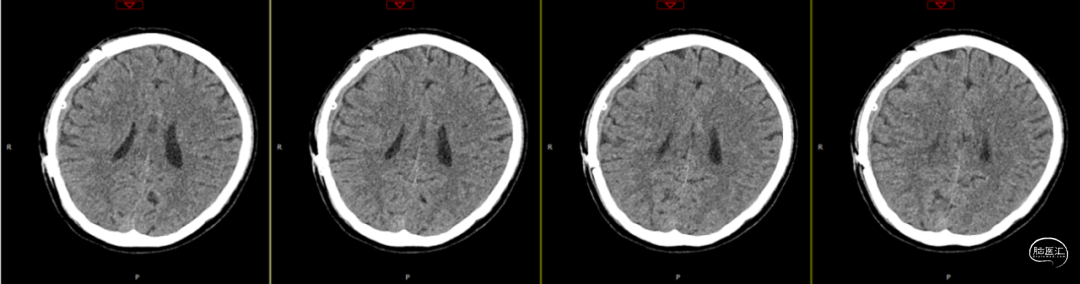

2024-07-21 08:58:55术后58天复查(如上图)。

术后58天颅脑磁共振平扫(如上图):右侧额顶颞部见斑片状异常信号,呈片状T1WI低、T2WI稍高信号影,T2FLAIR呈稍高信号,边界清,右侧额顶颞叶脑组织受压,DWI(b=1000)呈混杂高信号,相应ADC呈混杂高信号影。